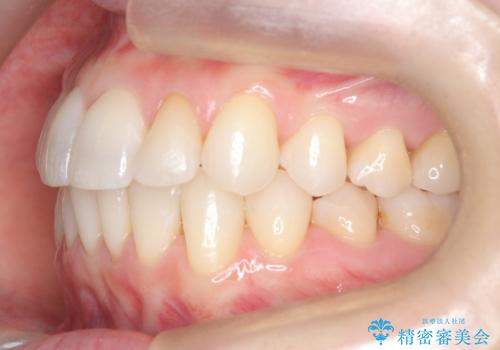

矯正後の後戻りで前歯にガタツキができてしまった インビザラインで改善

- 子どものときにワイヤー矯正をしていたが、後戻りによって前歯のガタツキが気になってきたとのことで来院されました。

アライナー矯正希望だったため、インビザラインによる治療を行いました。